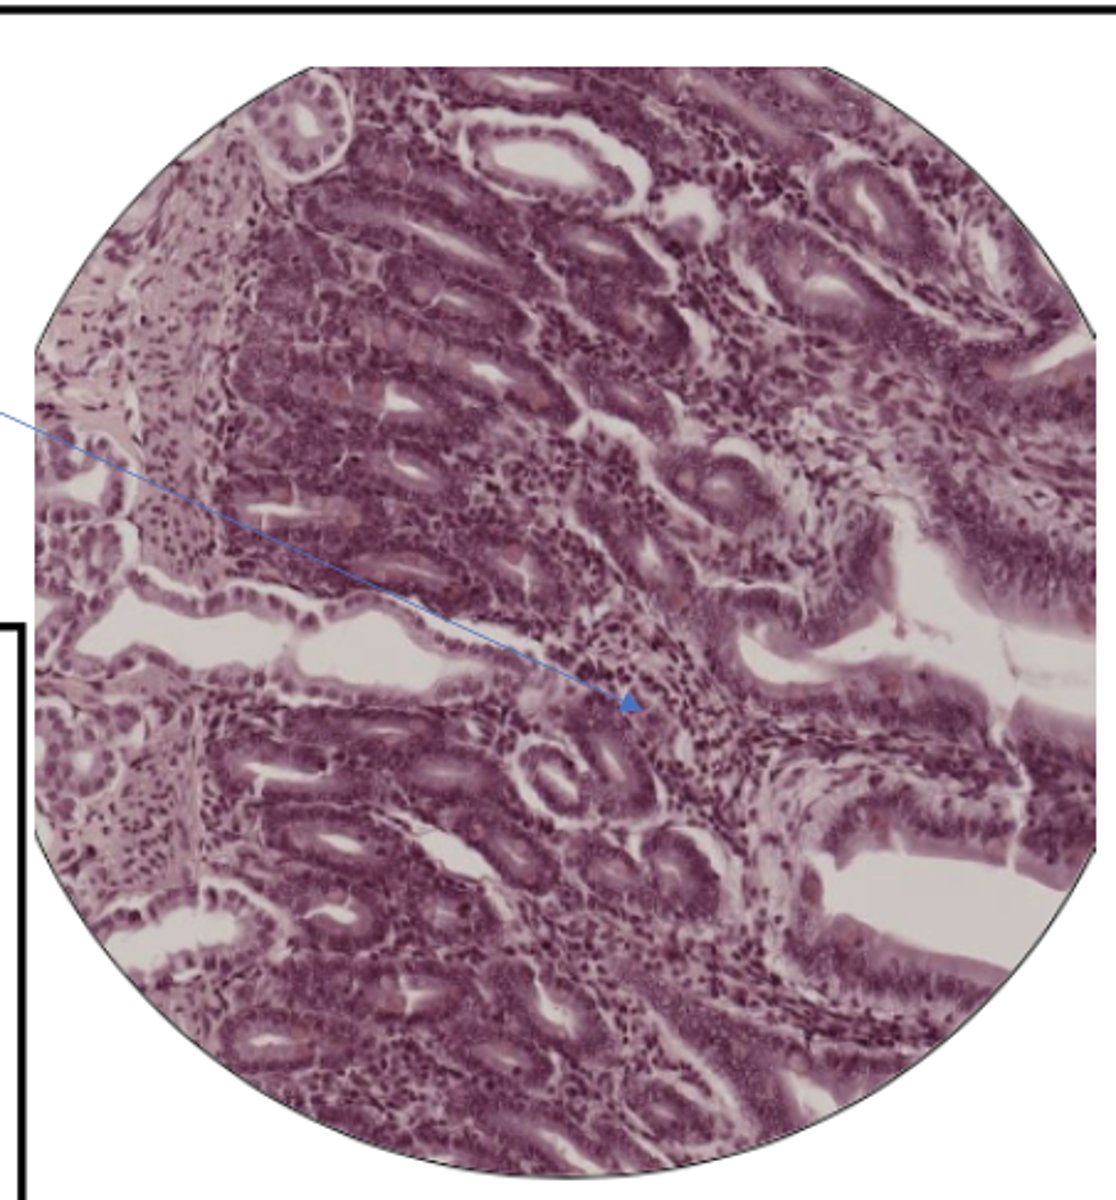

SI mucosa layer (100)

SI mucosa layer (400)